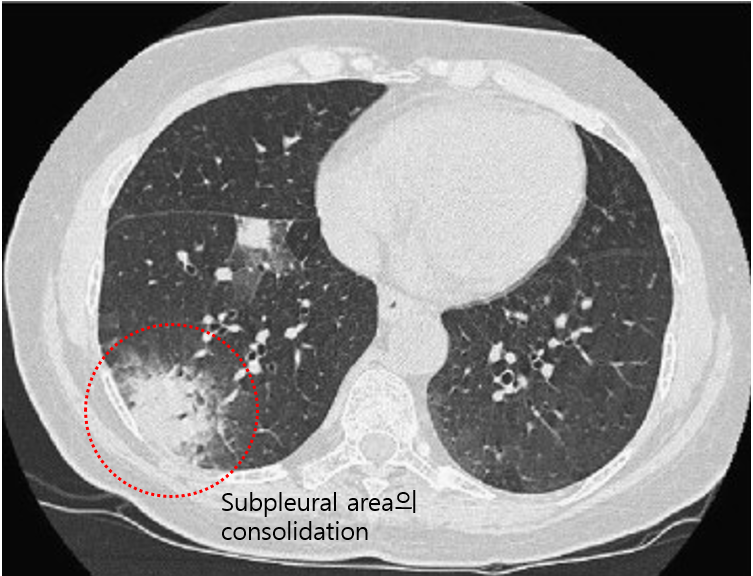

(2) 검사소견: Basal, subpleural/peribronchovascular consolidation